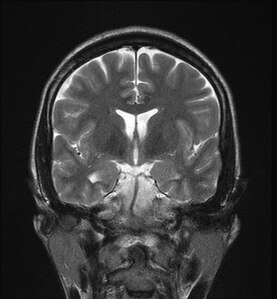

大脳 冠状断面<< 神経系 << バイオメディカル CG ライブラリー << 株式会社メタ・コーポレーション・ジャパン。

脳 MRI 3D : 正常解剖学e-Anatomy。

胸部CT冠状断 縦隔条件保険医療機関 医療法人 野口病院 ホームページ。

弁護士 小松亀一法律事務所_交通事故_MRI・CT写真の切り口用語解説。

ヘリカルCTは横断面だけではなく矢状面や冠状面も作ることができます!ふかつ泌尿器科・皮ふ科クリニック。